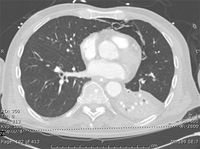

CT scan showing bibasilar opacities of patient with HAP

Consent obtained at University of Louisville, KY